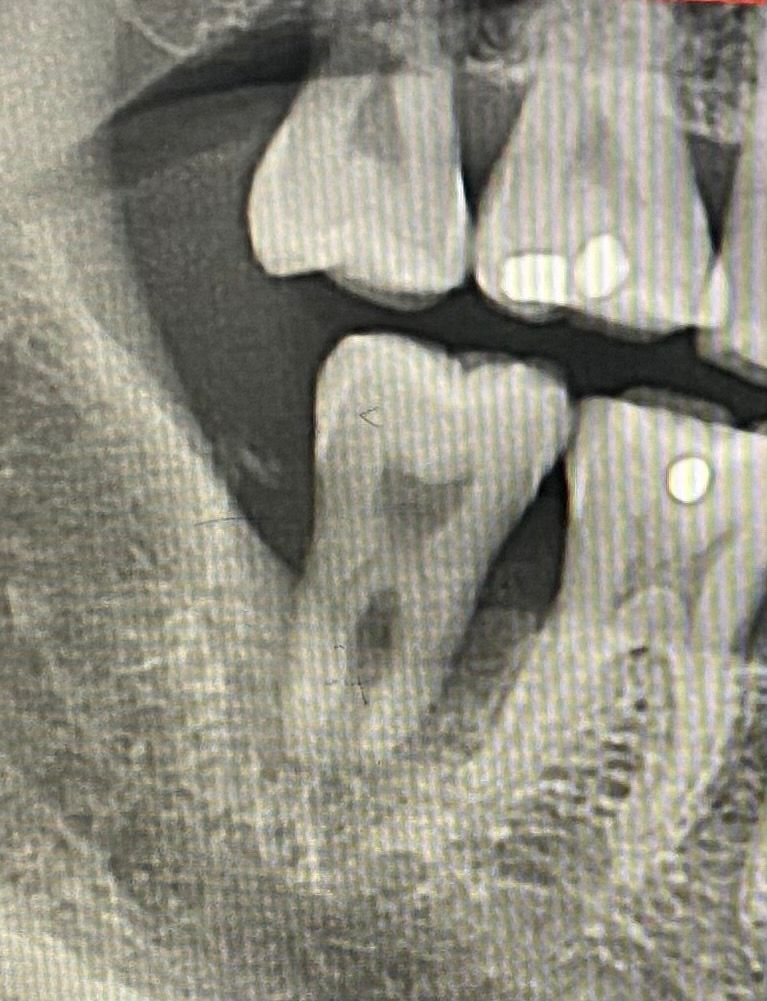

사진 치료 전후사진 첨부 드려요

• 2번 째 사진

위쪽치아가 많이 내려와보입니다. 정확한 상태를 알수는 없으나 위쪽. 치아를 건드려야 할 것 같습니다.

엑스레이 상으로는 크게 문제가 되는건 없는거 같습니다. 사진상으로 보면 임플란트 하는동안에 대합되는 치아가 약간 정출된거 같으니 교합조정을 다시 받아보시는게 좋을것같습니다.